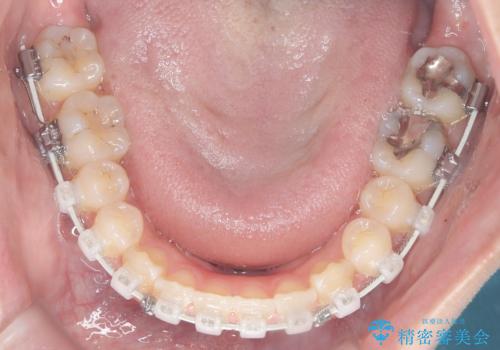

治療では、審美ワイヤーを使用し、目立ちにくく配慮しながら矯正を進めました。上顎にリンガルアーチと矯正用アンカースクリューを用いて臼歯部を安定的に遠心移動させ、歯列全体のスペースを確保しました。その後、回転していた前歯を正しい位置に配列し、全体的な歯並びの改善を行いました。治療中は、装置の適切な管理と口腔衛生を徹底することが重要でした。結果として、見た目だけでなく機能的にも優れた歯列を実現することができ、患者様にもご満足いただけました。